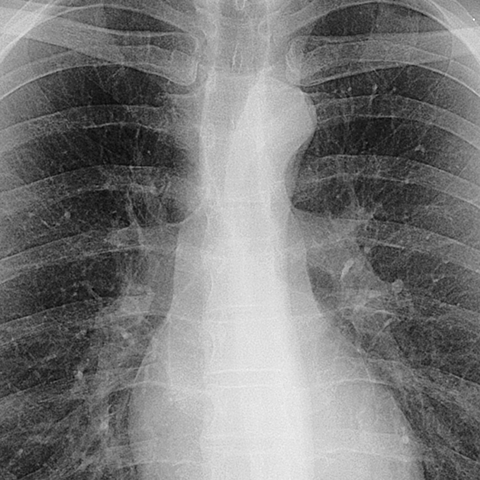

Normal Mediastinum, Aortopulmonary Window (PA CXR) [1 of 5]